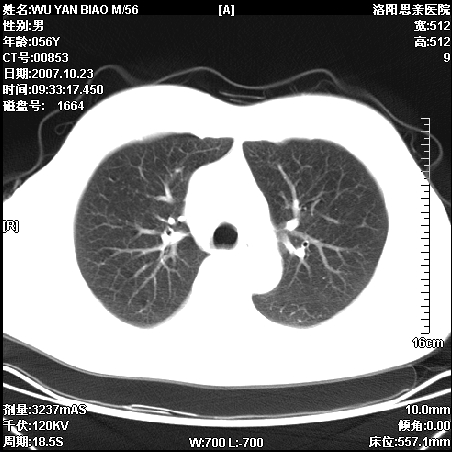

标题: CT10160:M56Y,体检发现,病人无不适,病人随访中 [打印本页]

标题: CT10160:M56Y,体检发现,病人无不适,病人随访中

后上纵隔占位,与肺交界清,宽基底附着脊柱,密度均匀,局部骨质无明确改变.

考虑;神经源性肿瘤,---起源交感n链?,不除外肠源性囊肿.

1、病灶在后纵隔脊柱旁沟内,此处是神经原性肿瘤的好发部位

2、病灶边缘光滑整齐,更说明病灶来于纵隔,由于有胸膜的包裹所以才导致这么光滑的边缘

3、病灶内的密度均匀